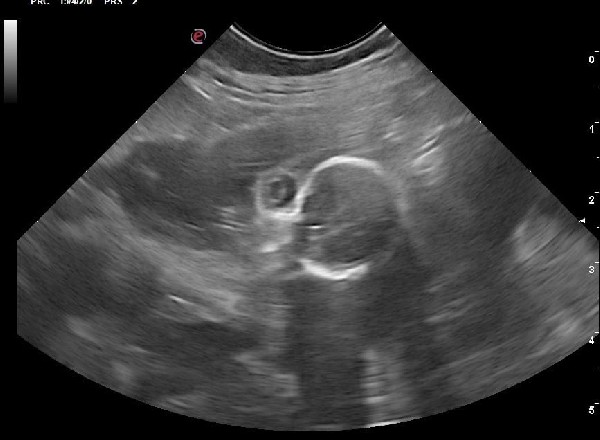

Le diagnostic de gestation est toujours un moment important. Si des tests de grossesse peuvent exister, l’examen de choix reste l’échographie.

En plus de confirmer la gestation, elle permet de contrôler l’aspect des ampoules, des placentas, des ovaires et de l’utérus. Elle permet aussi d’estimer avec une bonne précision le nombre de chiots si elle est faite au moment optimal (autour de J25 post-ovulation). Si la date d’ovulation n’est pas connue, l’échographie peut permettre de dater la gestation grâce à différentes mesures anatomiques et à l’évolution des structures anatomiques visibles à l’échographie. Elle permet également de mettre en évidence et de suivre d’éventuelles résorptions embryonnaires et nous amène alors à réaliser d’autres examens.